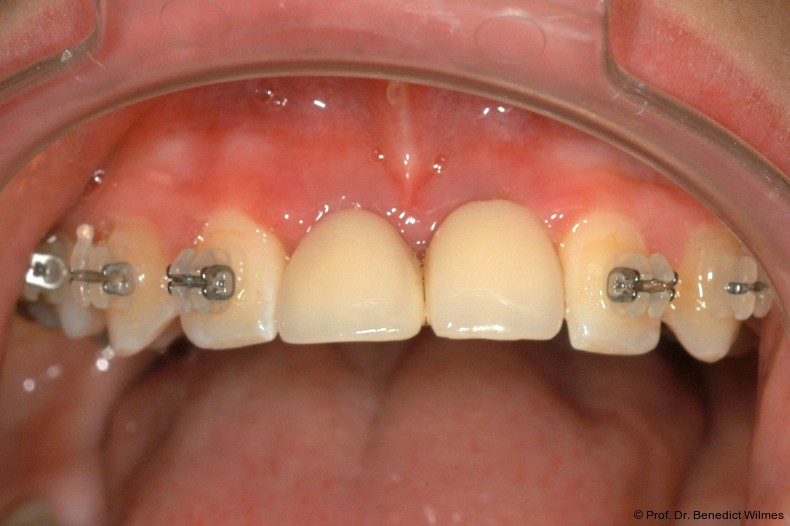

Ein 14-jähriger Patient wurde bei Aplasie der beiden oberen seitlichen Schneidezähne mit dem Ziel der beidseitigen Lückenöffnung kieferorthopädisch therapiert (Abb. 1a+b). Zum Ende der kieferorthopädischen Behandlung wurden zwei Miniimplantate in Regio 2er als temporärer Zahnersatz inseriert (Benefit System, PSM, 2 x 13 mm, Abb. 2a+b). Nach Abdrucknahme wurden Kronen auf den Peek-Abutments modelliert und diese mit Kunststoff auf die Abutments geklebt (Abb. 3a–d). In den Abbildungen 3 und 4 sind die klinischen und röntgenologischen Nachkontrollen innerhalb der nächsten achteinhalb Jahre dokumentiert. Man erkennt einen sowohl in der Höhe als auch in bukkopalatinalen Breite verbleibenden gesunden Knochen ohne Anzeichen einer Atrophie. Im Alter von 23 Jahren wurden die definitiven Implantate ohne die Notwendigkeit einer Augmentation eingesetzt (Abb. 5) und nach Einheilung prothetisch versorgt (Abb. 6a–e und Abb. 7a–c).